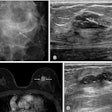

Images depict a 65-year-old patient with contralateral second breast cancer 6.3 years after right mastectomy. (A) Left craniocaudal and (B) mediolateral oblique mammograms assessed as benign. (C) The AI algorithm outlined a lesion with a score of 31 on the craniocaudal view. (D) A supplemental axial ultrasound scan, which was obtained on the same day as the mammogram, shows an irregular hypoechoic mass (arrows) in the left upper central breast. (E) Preoperative sagittal contrast-enhanced T1-weighted MRI scan shows the corresponding enhancing mass (arrow) in the left upper center. The mass was proven to be ductal carcinoma in situ.RSNA